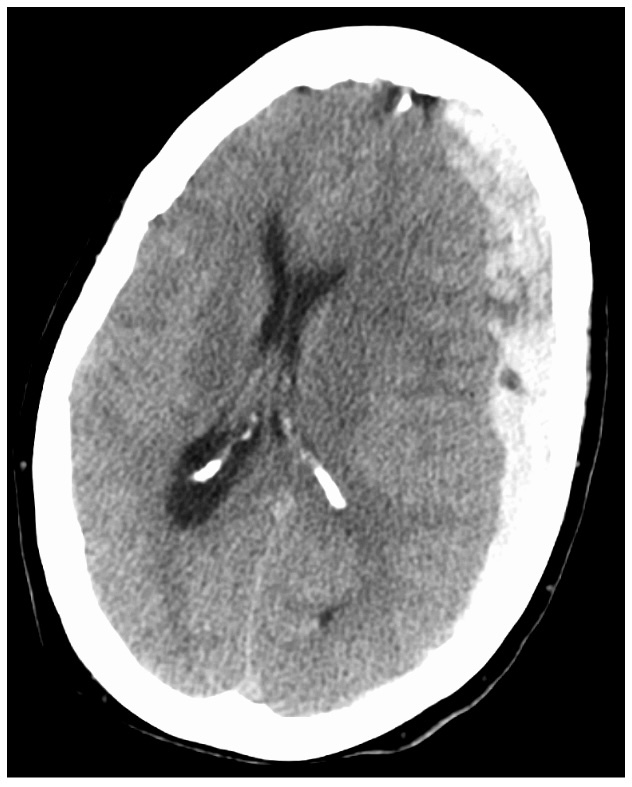

what does this CT head show?

A

left subdural haematoma

- crescent hyperdense mass

- midline shift

- not limited by sutures